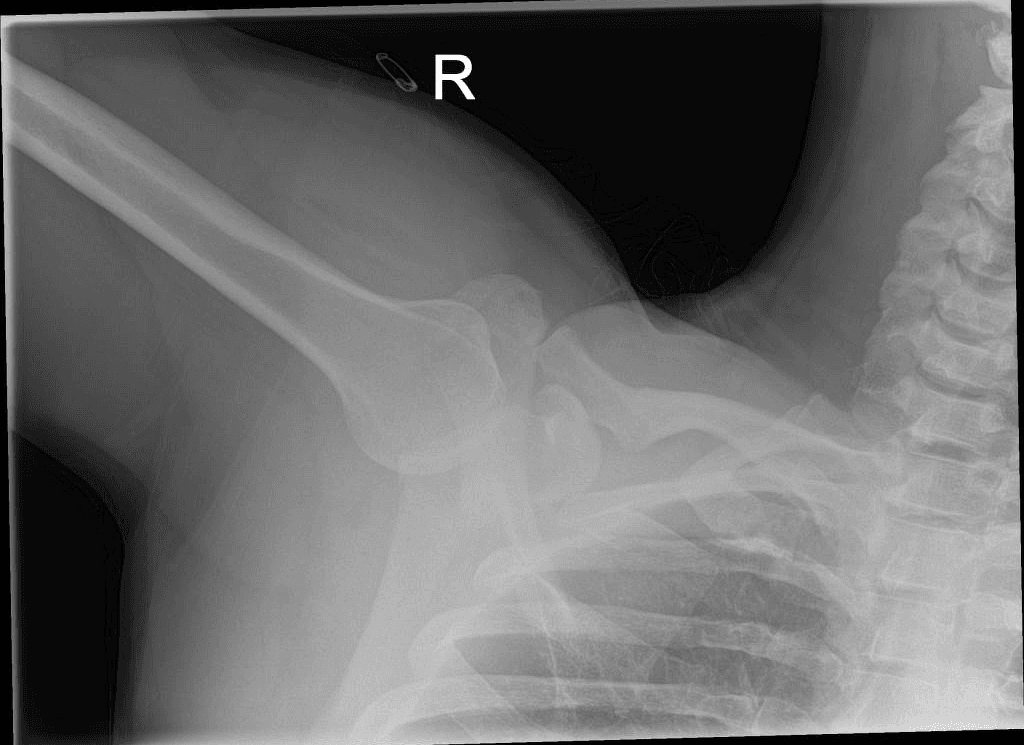

Trật khớp vai trước hai bên

Bệnh nhân bị hành hung. Nhập viện với tình trạng đau khớp vai hai bên và hạn chế vận động.

X-quang tại giường xác nhận trật khớp vai trước hai bên kèm theo khuyết xương Hill-Sachs. Các khớp vai khác bình thường. X-quang sau nắn xác nhận nắn chỉnh thành công các chỏm xương cánh tay kèm theo khuyết xương Hill-Sachs hai bên, đặc biệt rõ ở bên trái. THẢO LUẬN: Các đặc điểm phù hợp với trật khớp vai trước hai bên thứ phát sau chấn thương cùn trong một vụ hành hung nạn nhân. Rối loạn co giật là nguyên nhân phổ biến nhất gây trật khớp vai hai bên. Điện giật cũng có thể gây trật khớp vai hai bên. Trong cả hai trường hợp này, đây thường là trật khớp vai sau, tuy nhiên đôi khi cũng xảy ra trật khớp vai trước. Chấn thương trực tiếp là một nguyên nhân phổ biến gây trật khớp vai trước hai bên.